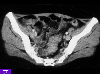

A case of intestinal endometriosis with severe stenosis of the sigmoid colon.

CT

Tumor-like lesions/Endometriosis